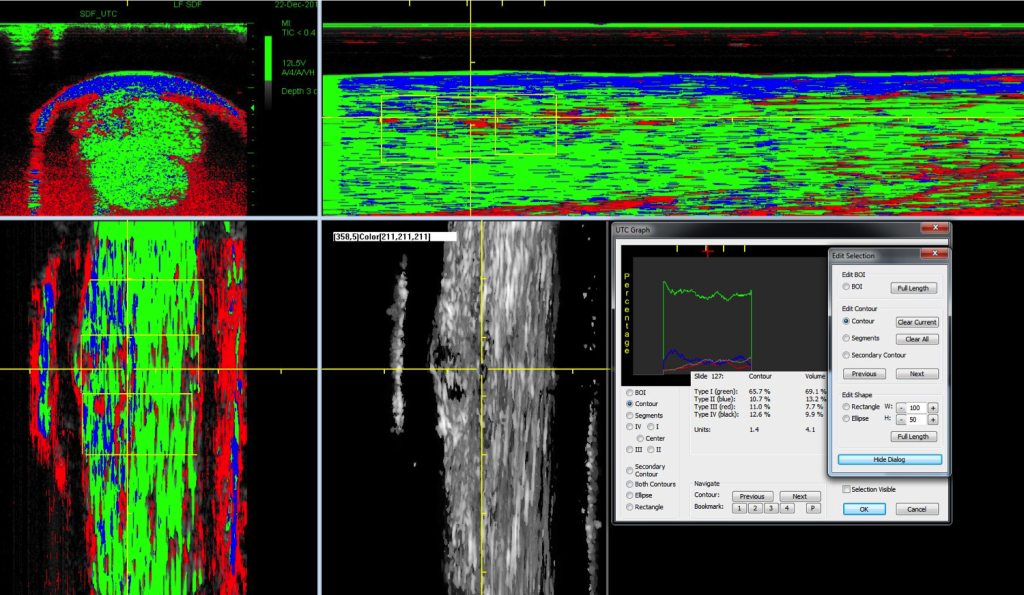

UTC met kleurcodering

UTC-kleurcodering

1. groen voor normaal gerangschikte peesbundels

2. blauw voor meer golvende peesbundels

3. rood voor fibrillaire (kleinere/onvolwaardige) bundels

4. zwart voor met name vocht

Daarnaast kan er aan elk van deze weefsels een percentage gegeven worden. Hierdoor geeft de scan naast een duidelijk beeld van de kwaliteit van de pees ook meetbare resultaten, die één op één vergeleken kunnen worden met eerdere scans van het paard.